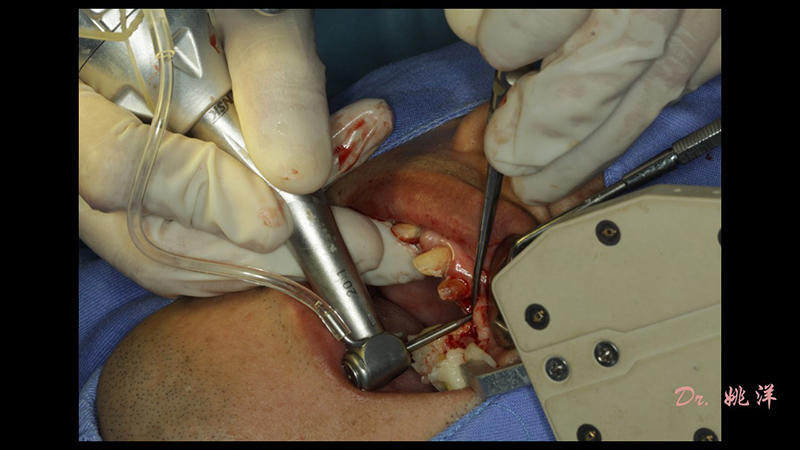

術(shù)中操作

導(dǎo)航下精細(xì)分配修復(fù)間隙,精細(xì)規(guī)劃植入方向,避開上頜竇底,精確植入

今天,小迪就給大家?guī)硪粓鲇扇A西口腔醫(yī)院姚洋博士主刀、迪凱爾主動式紅外光種植手術(shù)導(dǎo)航作為輔助工具的前牙烤瓷冠種植修復(fù)手術(shù)病例!